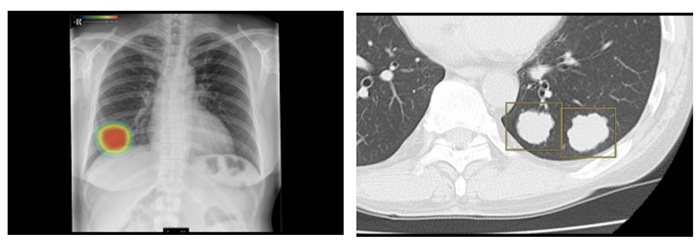

さらに、複数の読影支援機能を、専用ポータルサイトから選択し利用できる「医療クラウドサービス」に対応した。クラウドサーバーにアップロードされた画像で、「胸部X線CADサービス」や「肺結節検出サービス」などの選択した読影支援機能の解析結果をビューワ上で参照できる。料金プランは、利用回数に応じた従量課金と、一定期間利用できる定額利用を用意する。